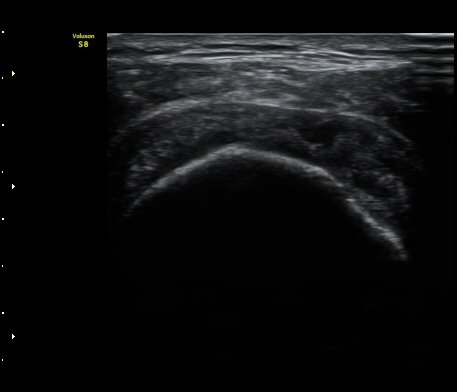

3°³¿ù ÈÄ ÃßÀû°Ë»ç

2049205267_a5fe3a8a_US181253111.jpg

2049205267_e81a53aa_US181338113.jpg